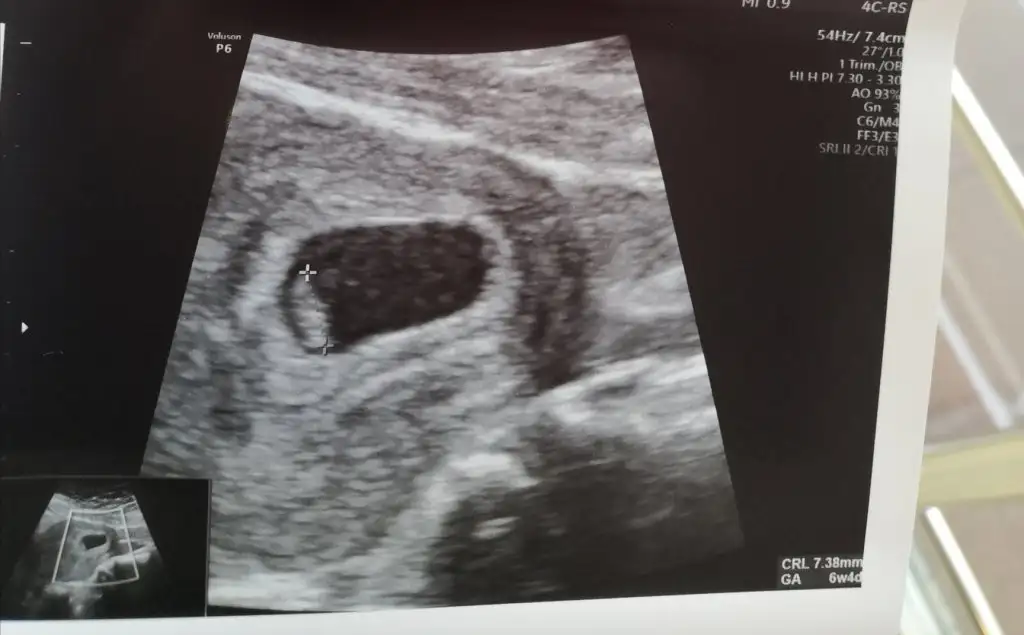

Peki benimkine bakabilirmisnzRamzi teorisine göre ( bilimsel bir araştırma sonucuymuş ve %85 doğruluğu varmış). İlk 6-8 haftalık ultrason görüntüsüne göre bebeğin kesenin içersinde soldan ya da sağdan girişine göre cinsiyet tahmini yapılıyor. Bilimsel olunca tecrübeli annelerimiz yada anne adaylarımızdan yardım istiyoruz. Doğruluğu var mı öğrenmek adına :) Bizleri aydınlatırsanız çok seviniriz. bu teorieye göre;

Karından bakıldıysa eğer,

Soldan girmiş gözüküyosa gerçektede solmuş ve ERKEK,

Sağdan girmiş gözüküyosa gerçekte de sağmış ve KIZ,